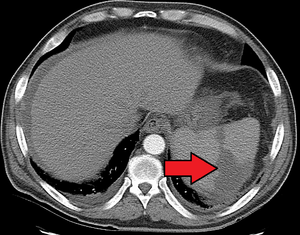

| Splenic infarct seen on CT | |

Splenic infarction is a condition in which oxygen supply to the spleen is interrupted, leading to partial or complete infarction (tissue death due to oxygen shortage) in the organ.[1]

Splenic infarction occurs when the splenic artery or one of its branches are occluded, for example by a blood clot. Although it can occur asymptomatically, the typical symptom is severe pain in the left upper quadrant of the abdomen, sometimes radiating to the left shoulder. Fever and chills develop in some cases.[2] It has to be differentiated from other causes of acute abdomen.

An abdominal CT scan is the most commonly used modality to confirm the diagnosis,[2] although abdominal ultrasound can also contribute.[3][4][5]